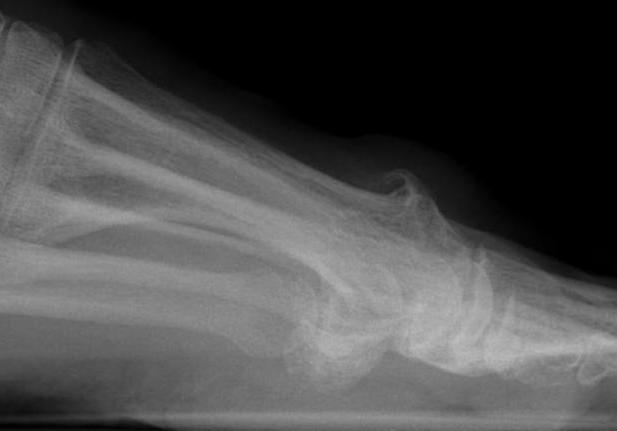

X-ray

Osteoarthritis

- joint space narrowing

- dorsomedial osteophyte

Mild to moderate OA

Severe OA